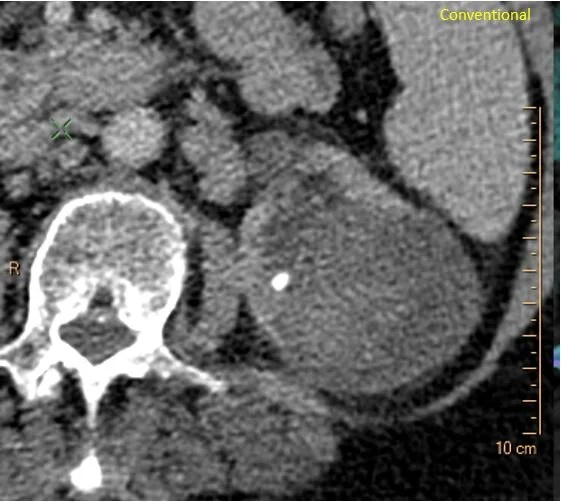

80 yo F presents to the ER with flank pain. CT scan of the abdomen is ordered. There is a complex heterogeneous mass in the left kidney, and a left kidney stone.

Conventional CT: Complex cystic and solid mass in left kidney and kidney stone.

Solid component is about 40 HU in density on conventional